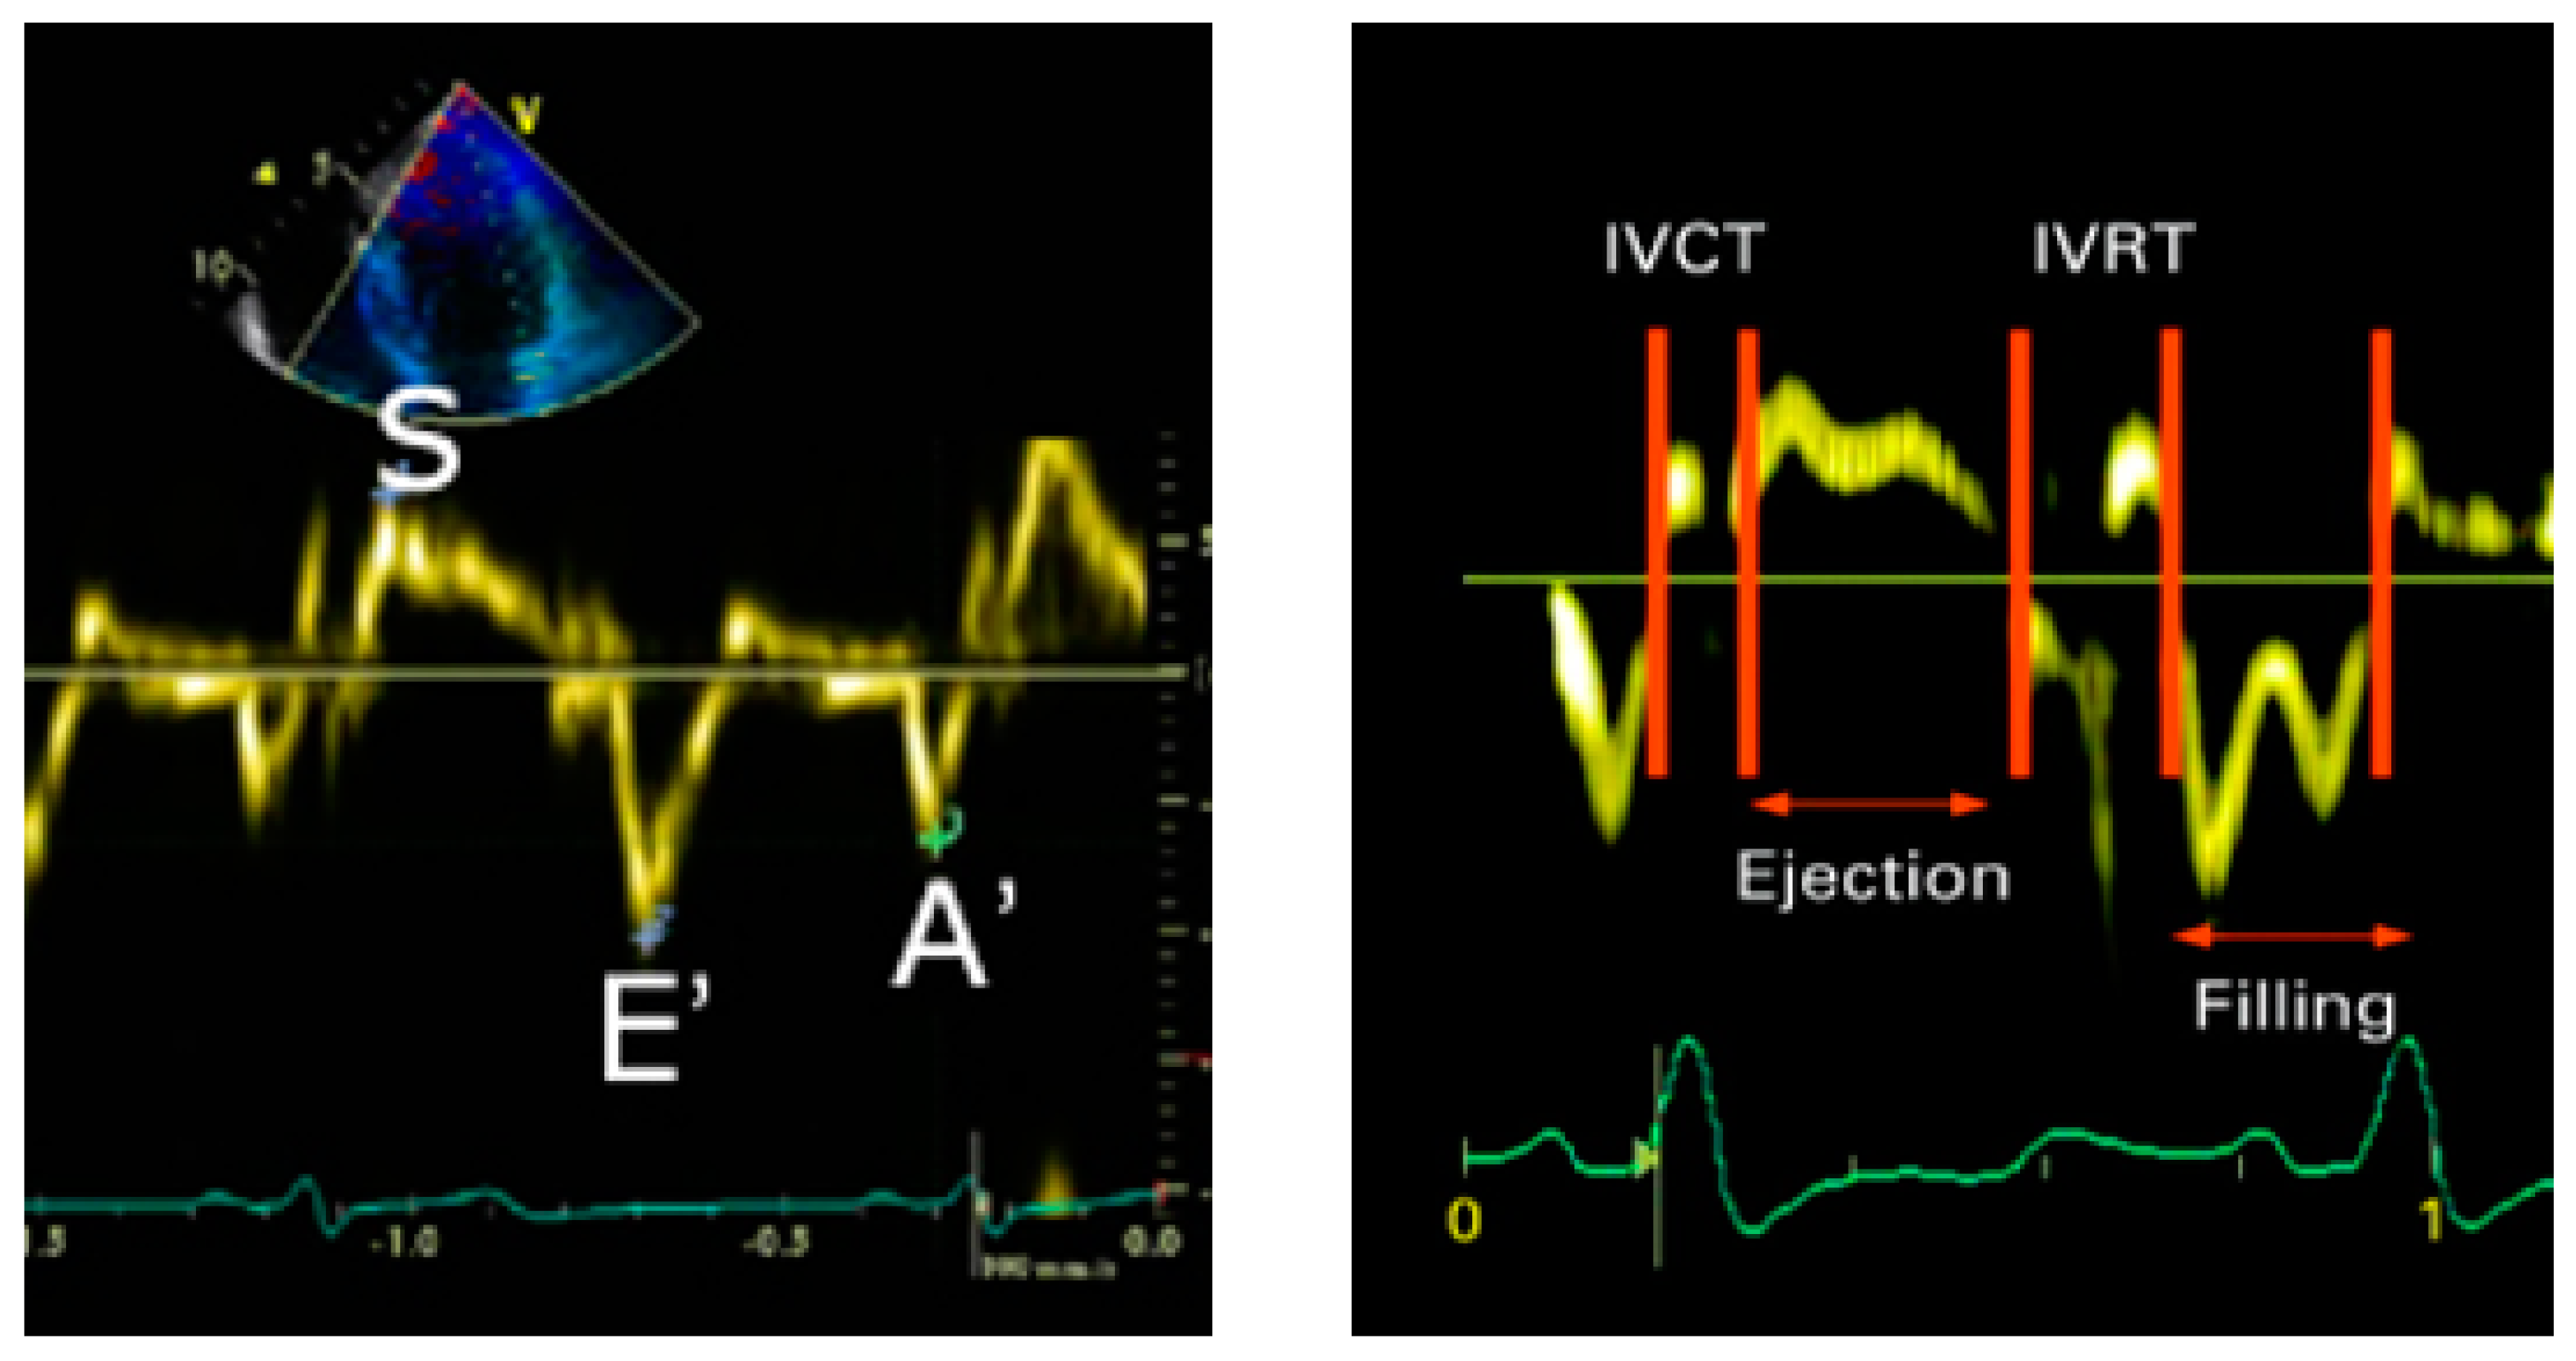

2.3. Maternal and Childhood Cardiovascular Assessment

| Diastolic Indices | |||

| Mitral valve E (cm/s) | 23.7 (3.8) | 25.3 (3.4) | 0.084 |

| Mitral valve A (cm/s) | 15.2 (3.1) | 15.9 (3.6) | 0.340 |

| Mitral valve E/A | 1.8 (0.6) | 2.2 (0.9) | 0.018 |

| Mitral valve E/e′ | 3.6 (0.8) | 3.1 (0.9) | 0.022 |

| Systolic Indices | |||

| Myocardial-performance index | 0.49 (0.1) | 0.43 (0.1) | 0.059 |

| Mitral valve S | 18.1 (2.8) | 19.6 (3.0) | 0.036 |